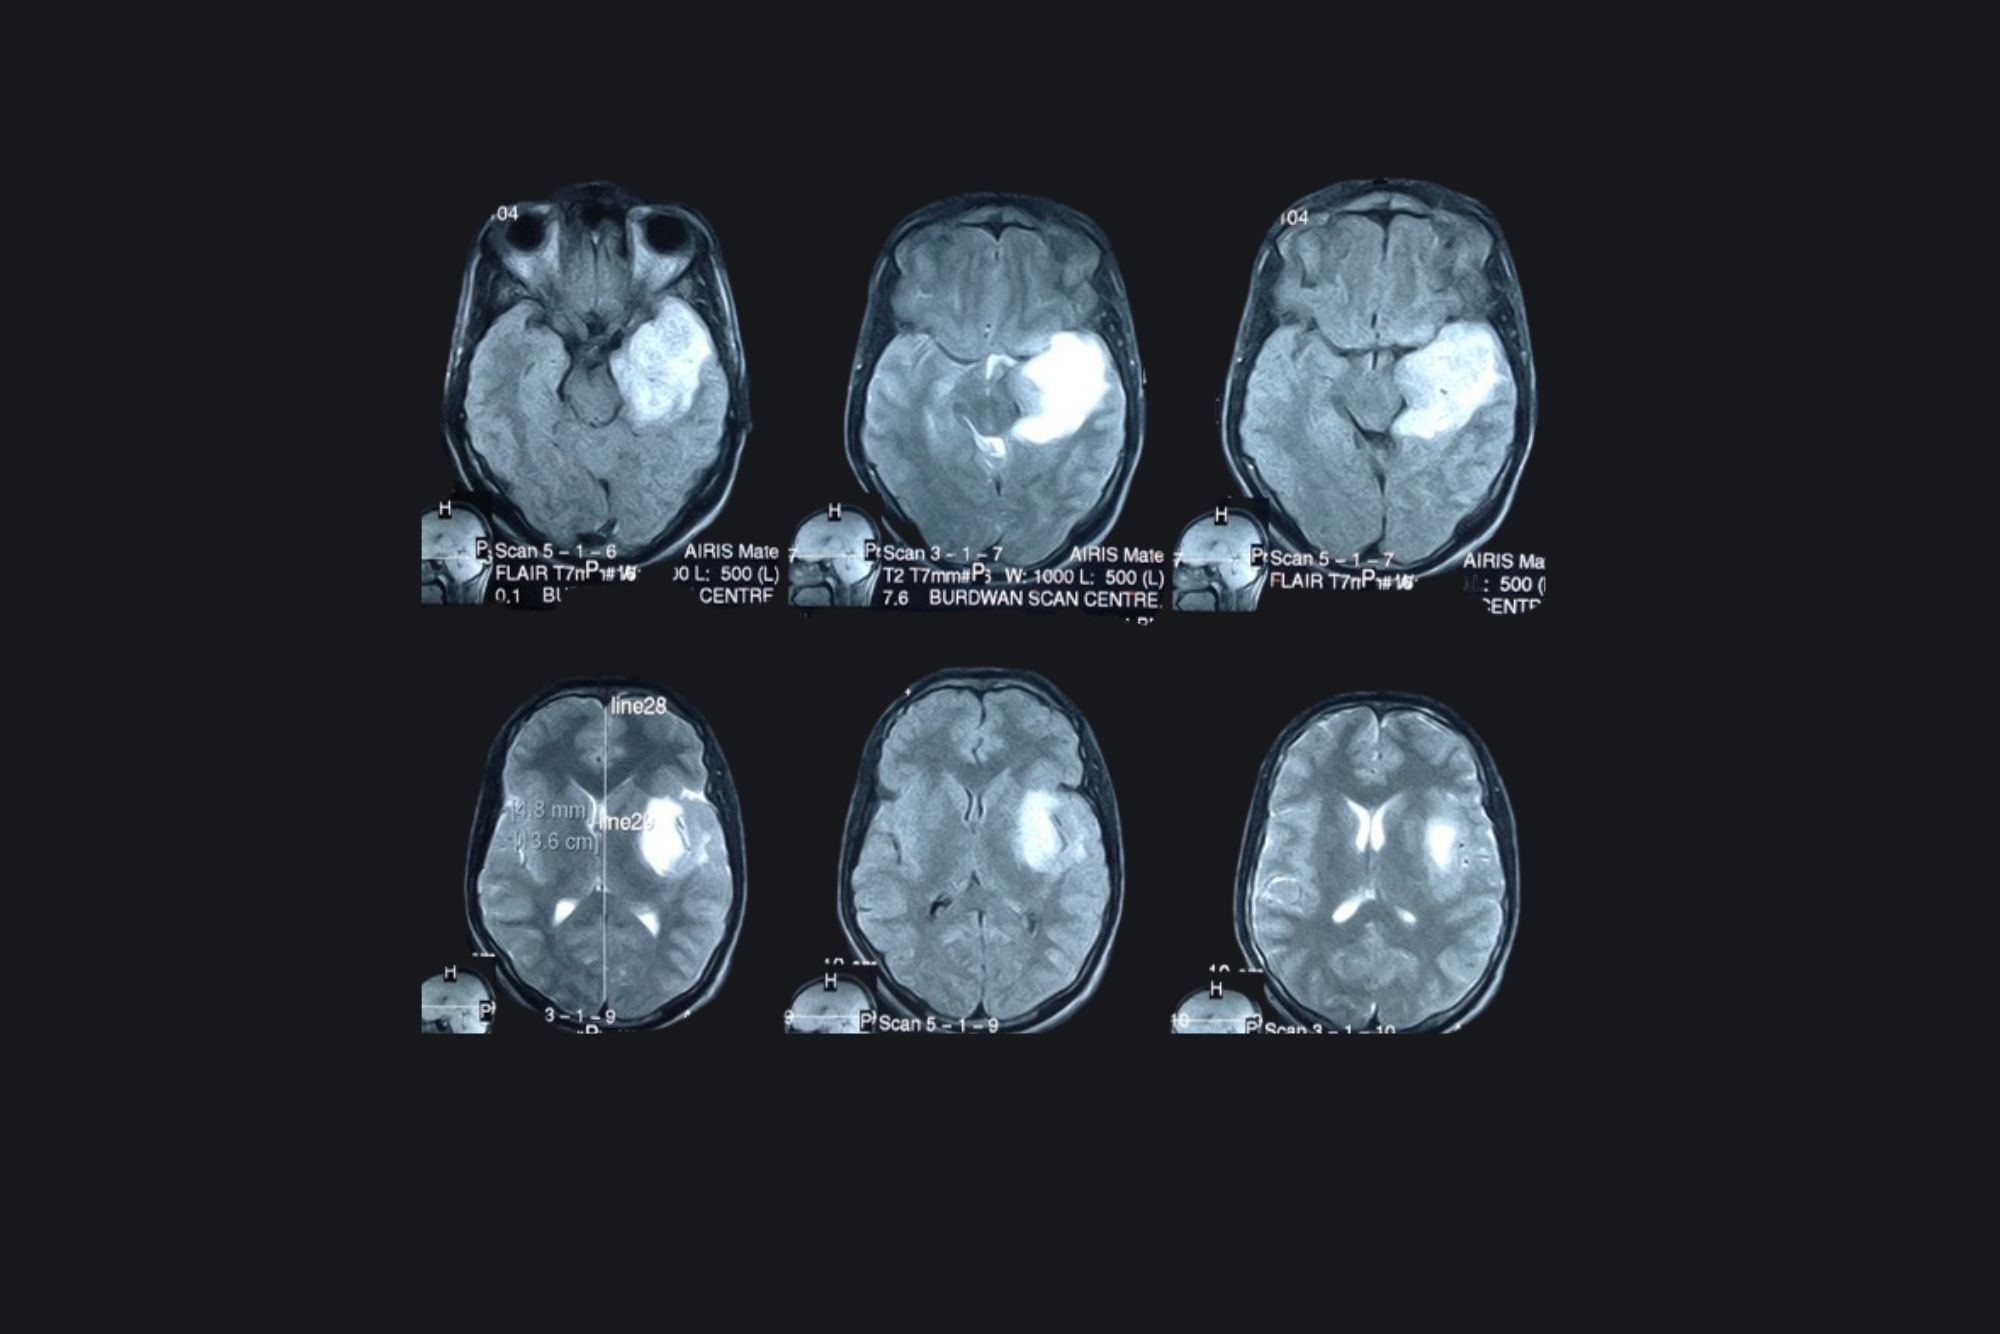

Cavernoma

Preoperative MRI

1 year Post operative contrast MRI